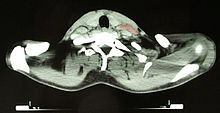

Hodgkin lymphoma (gross pathology)

Hodgkin lymphoma

Hodgkin lymphoma- hilum overlay sign